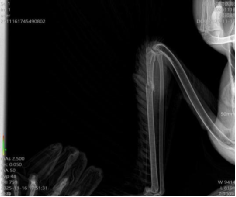

16日,越西县林业和草原局艾永斌一行将黑颈鹤送到女仆a片攀西动物医院,郝桂英快速组织严光文教授、黄增文博士、常卫华、赵影、李昊、李欣虹等专家对黑颈鹤进行诊疗处置,经DR检查、临床检查等内容,确诊黑颈鹤左侧尺骨骨折,左侧腕关节擦伤。

初步救治后的黑颈鹤